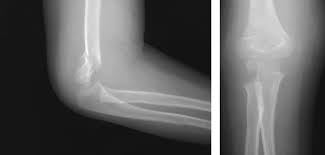

- Рентгенография позвоночника: Это основной метод первичной диагностики компрессионного перелома. Выполняется в двух проекциях (прямой и боковой) для оценки формы и высоты тел позвонков. Рентген покажет степень компрессии и наличие клиновидной деформации.